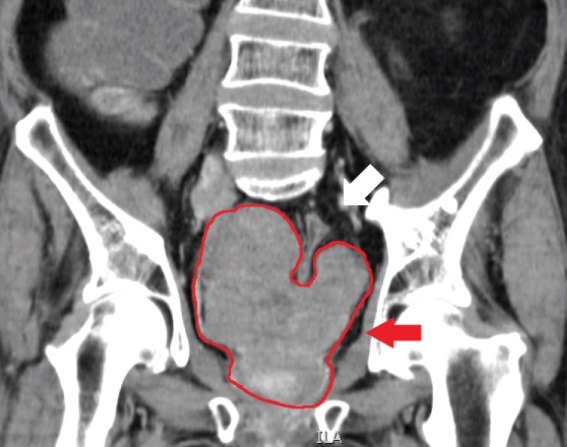

Examen de tomodensitométrie d'un cancer de la prostate chez un homme de 73 ans.

Source: https://en.wikipedia.org/wiki/File:CT_of_prostate_cancer.jpg